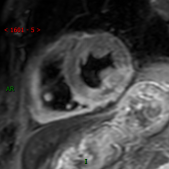

心脏增强磁共振(CMR)

心脏增强磁共振(CMR)是一种评估心肌健康状况的检查方法。虽然CMR无法直接观察冠状动脉的病变情况,但它能够对心肌的功能、结构和血流灌注提供详细的信息。CMR对于判断心肌是否存在缺血、纤维化、损伤等具有非常高的敏感性,因此它常用于冠心病发作后的恢复期评估,帮助医生判断心脏的恢复情况。此外,CMR还可以无创地评估心脏的收缩功能,适用于需要长期跟踪心脏健康状况的患者。

然而,CMR也有其局限性。首先,CMR对于冠脉狭窄的判断没有冠脉CTA那么精准,

因此不太用于冠心病的早期筛查。其次,由于CMR检查时间较长,且需要患者保持长时间静止,这对一些体弱或焦虑的患者来说,可能会增加检查的难度。

T2 STIR BB

PISR 10min